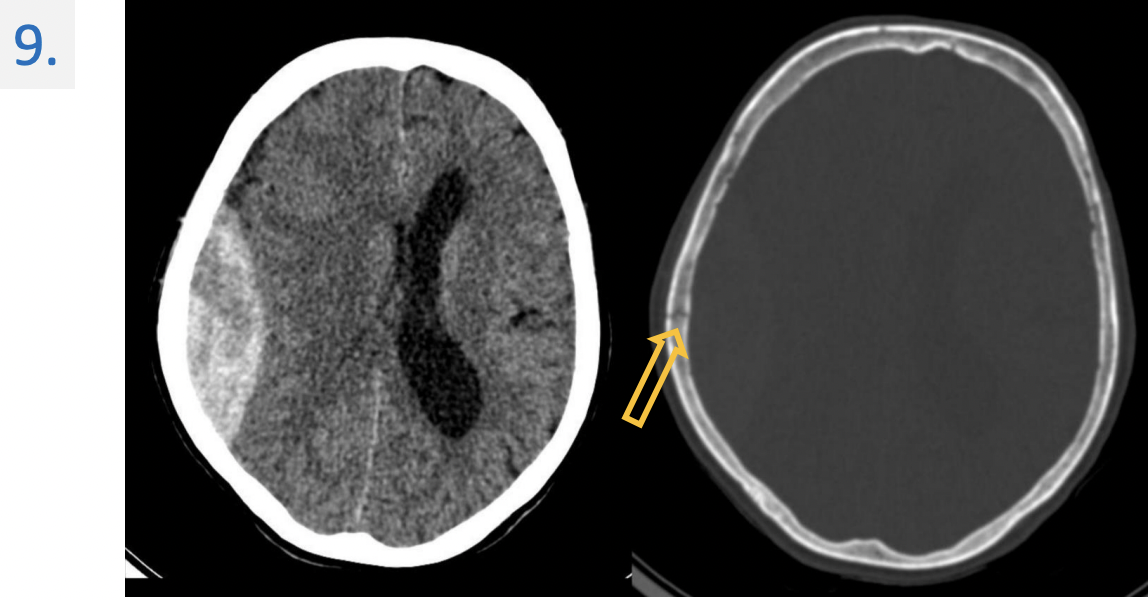

9.